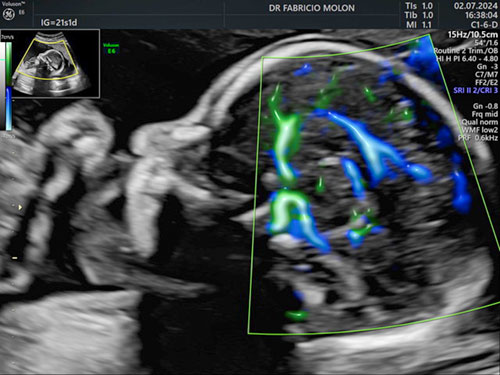

Dopplerfluxometria obstétrica

Um exame focado na análise da circulação da mãe e do bebê.

Algumas questões que vamos avaliar neste exame:

• A saúde da placenta;

• Indícios pré-eclâmpsia;

• Doença hipertensiva;

• Rastreamento de anemia fetal;

• Fluxo das artérias uterinas;

• Crescimento e movimentação fetal.